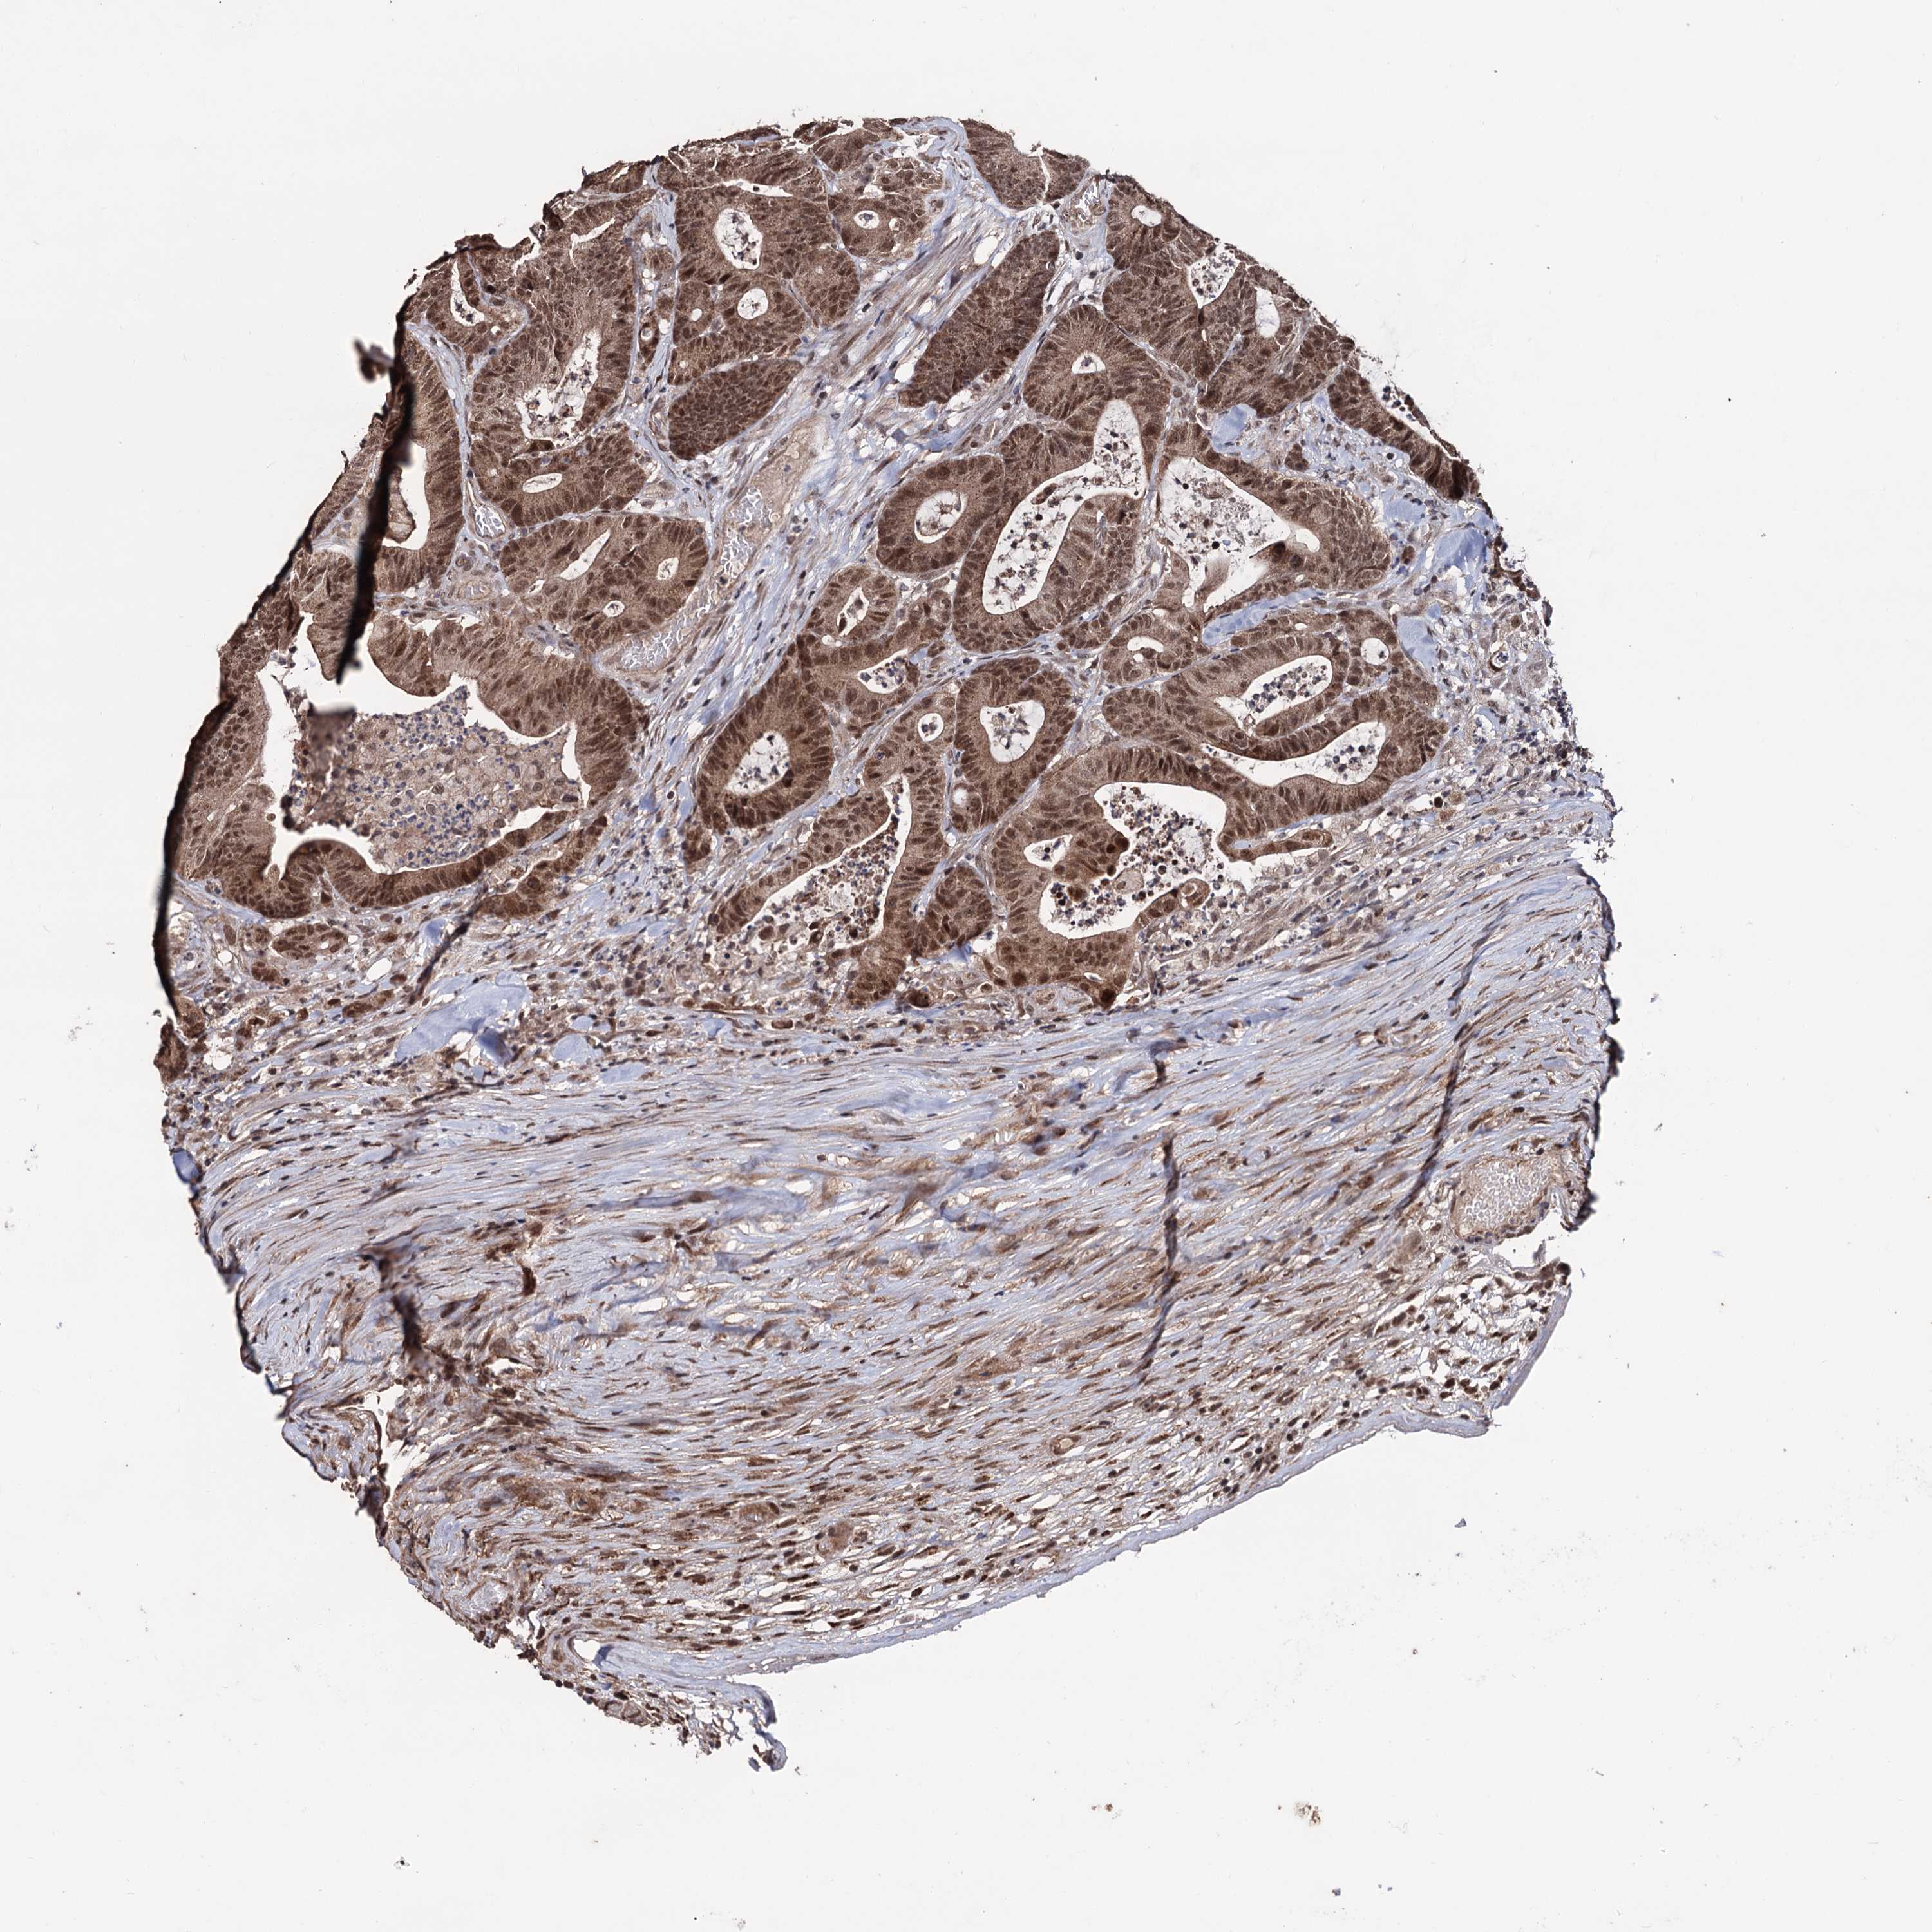

CANCER COLORECTAL CANCER Show tissue menu

Colorectal cancer

Human cancer

Colon adenocarcinoma